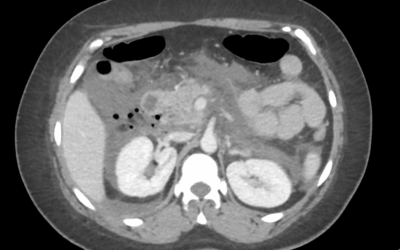

Caso de urgencias (I)

• Mujer de 35 años, sin antecedentes médicos de interés. No hábitos tóxicos. No toma tratamiento crónico. Colecistectomizada como único antecedente quirúrgico. • Ingresa para estudio de epigastralgia de un mes de evolución. No fiebre. Analíticas con elevación de...